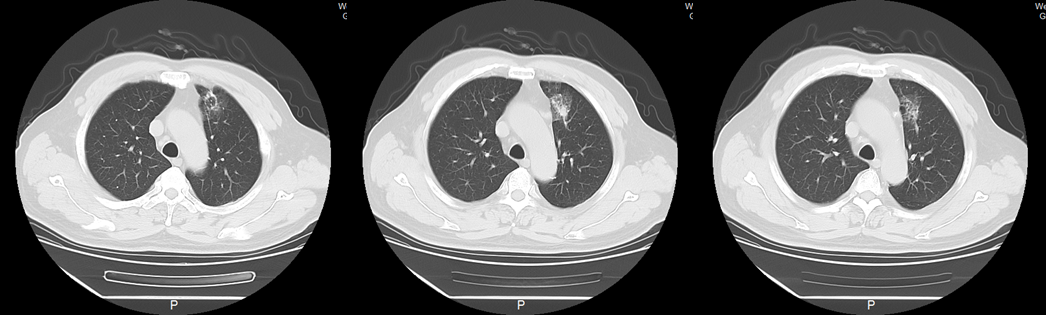

患者肢体肌力完全恢复,继续信迪利单抗+阿帕替尼治疗至2019年10月22日,共完成10个周期治疗。至今电话随访2次,目前患者拒绝再次治疗,截至末次随访(2019年12月),患者病情稳定,接受信迪利单抗联合阿帕替尼的治疗无进展生存期(PFS)超过8个月。

image008.png

图6.患者2019年7月29日胸部CT影像资料